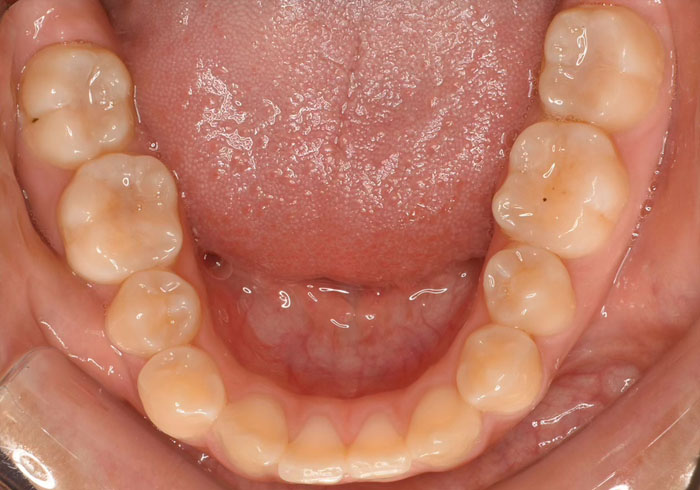

口腔内写真

治療後

マウスピース矯正 マウスピース矯正 マウスピース矯正